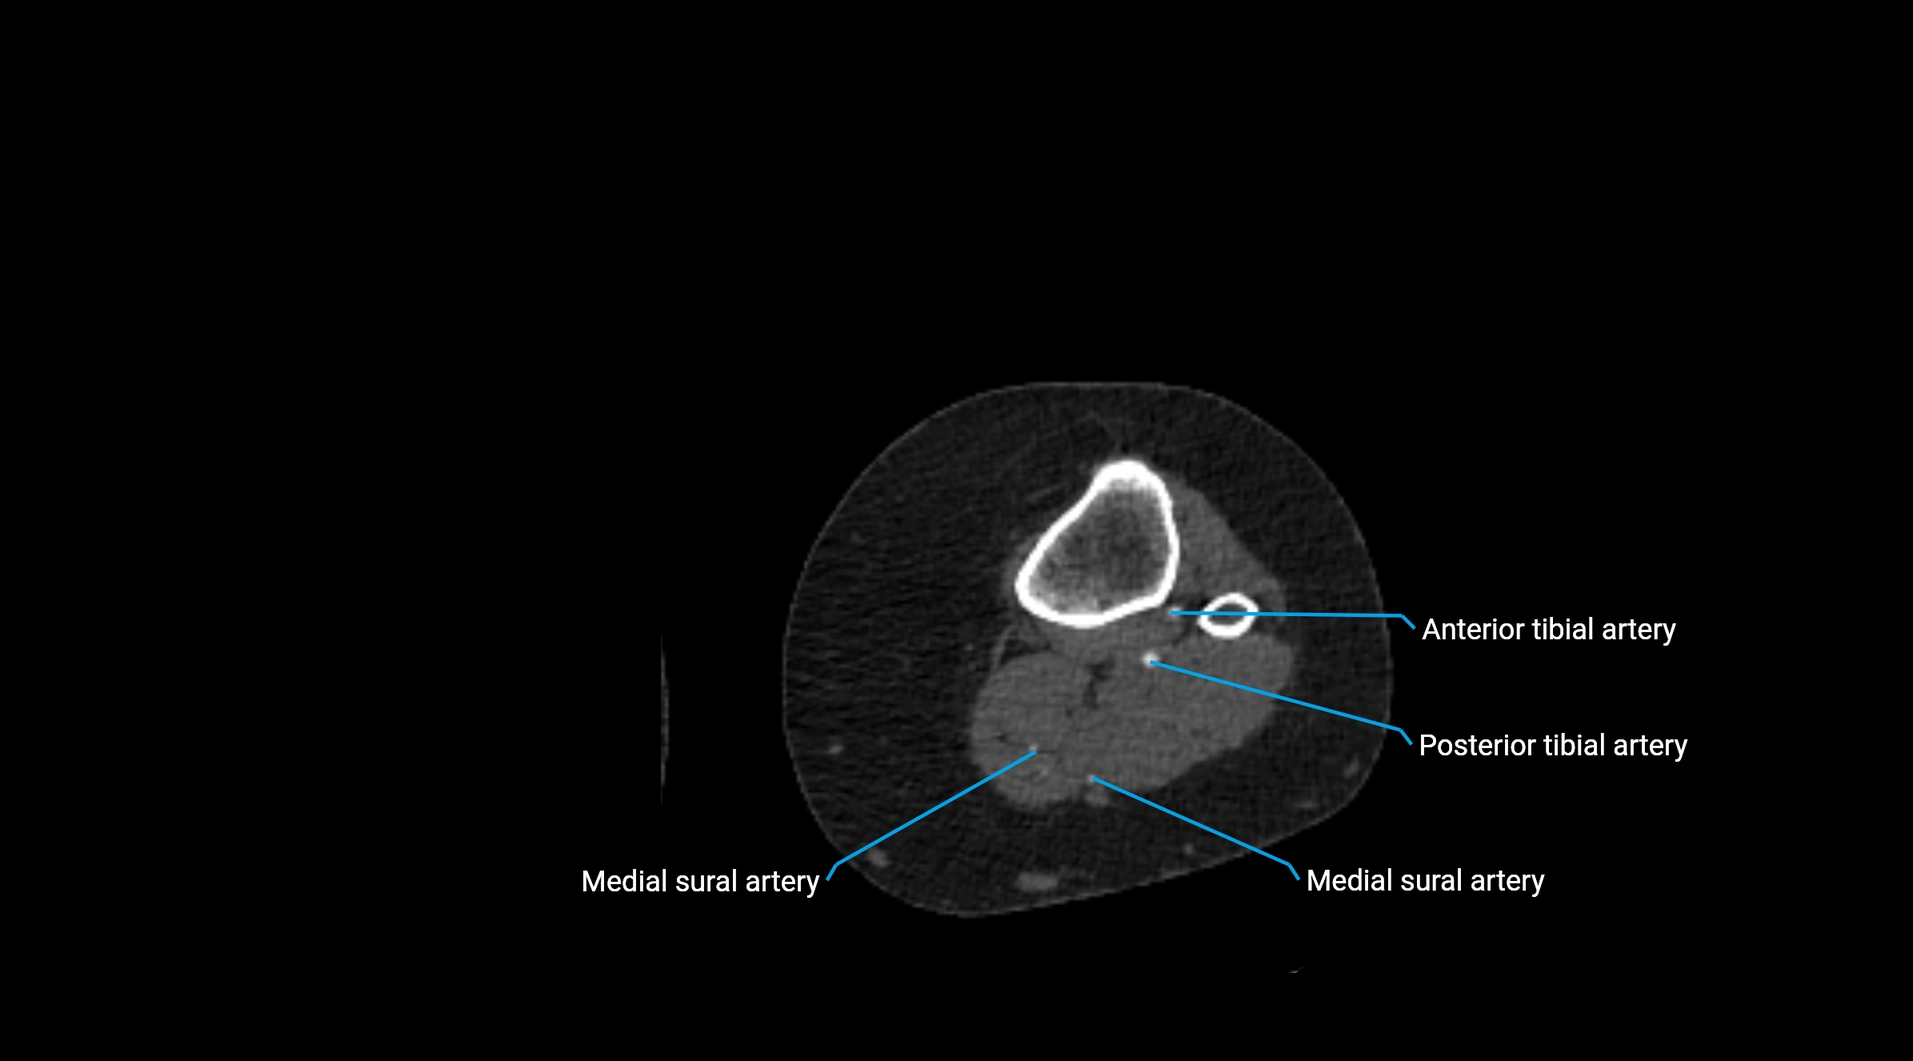

Contrast-enhanced CT (CTA):

• Gold standard for abdominal aortic imaging

• Provides excellent detail of lumen, wall, aneurysm, thrombus, and branch vessels

• Multiplanar and 3D reconstructions help in aneurysm measurement, stent graft planning, and dissection evaluation

CT images

image